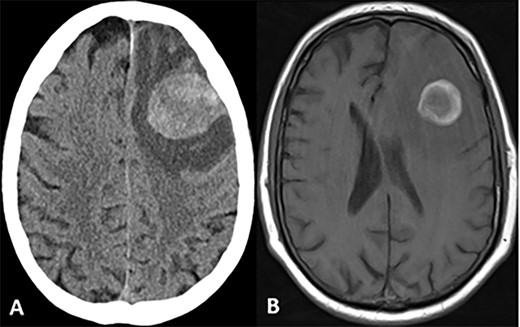

CASE

Postoperative CT and MRI scans of the head indicating complete tumor resection with reduced midline shift.